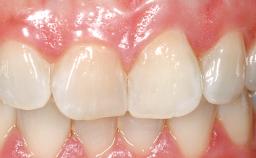

Immediate Placement of an Implant in a Maxillary Left Central Incisor Site

A 33-year-old female patient presented with an upper left central incisor that required extraction after a failed endodontic therapy. The tooth had been traumatized when the patient was a teenager and had undergone several endodontic treatments, including two apicectomy procedures. The patient was in good health and did not smoke. Clinical examination showed that the patient had a high lip line. In full smile, the gingival margins of the upper teeth were visible to the first molars. The gingival margins of central incisors 11 and 21 were only just showing. Examination of tooth 21 confirmed that the tooth was mobile and had hypererupted by 1 mm.

Prosthesis Type FDP

Lip Line No exposure of papillae Exposure of papillae Full exposure of mucosa margin

Periodontal Phenotype Low-scalloped, thick Medium-scalloped, medium-thick High-scalloped, thin